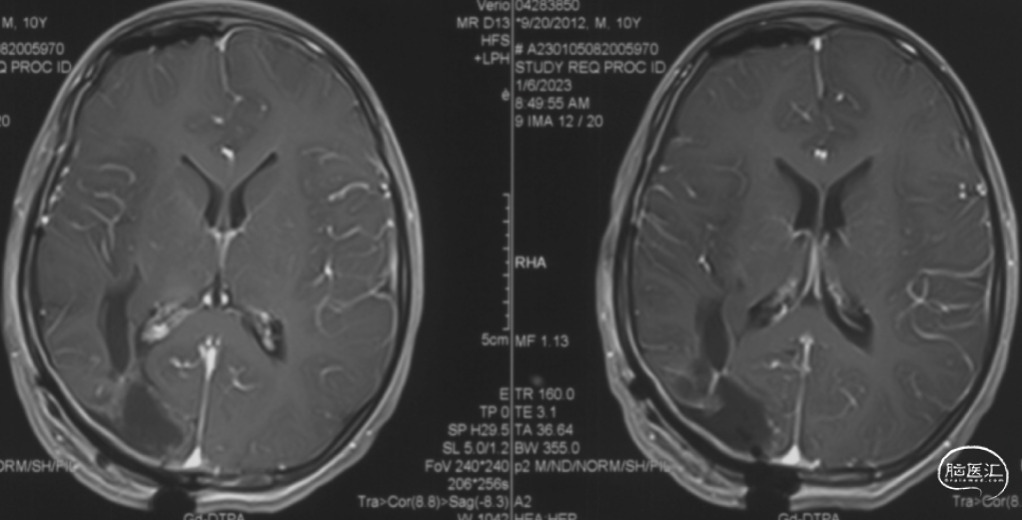

术后增强MRI、CT

增强MRI未见明显AVM残留,右顶缺损修补满意